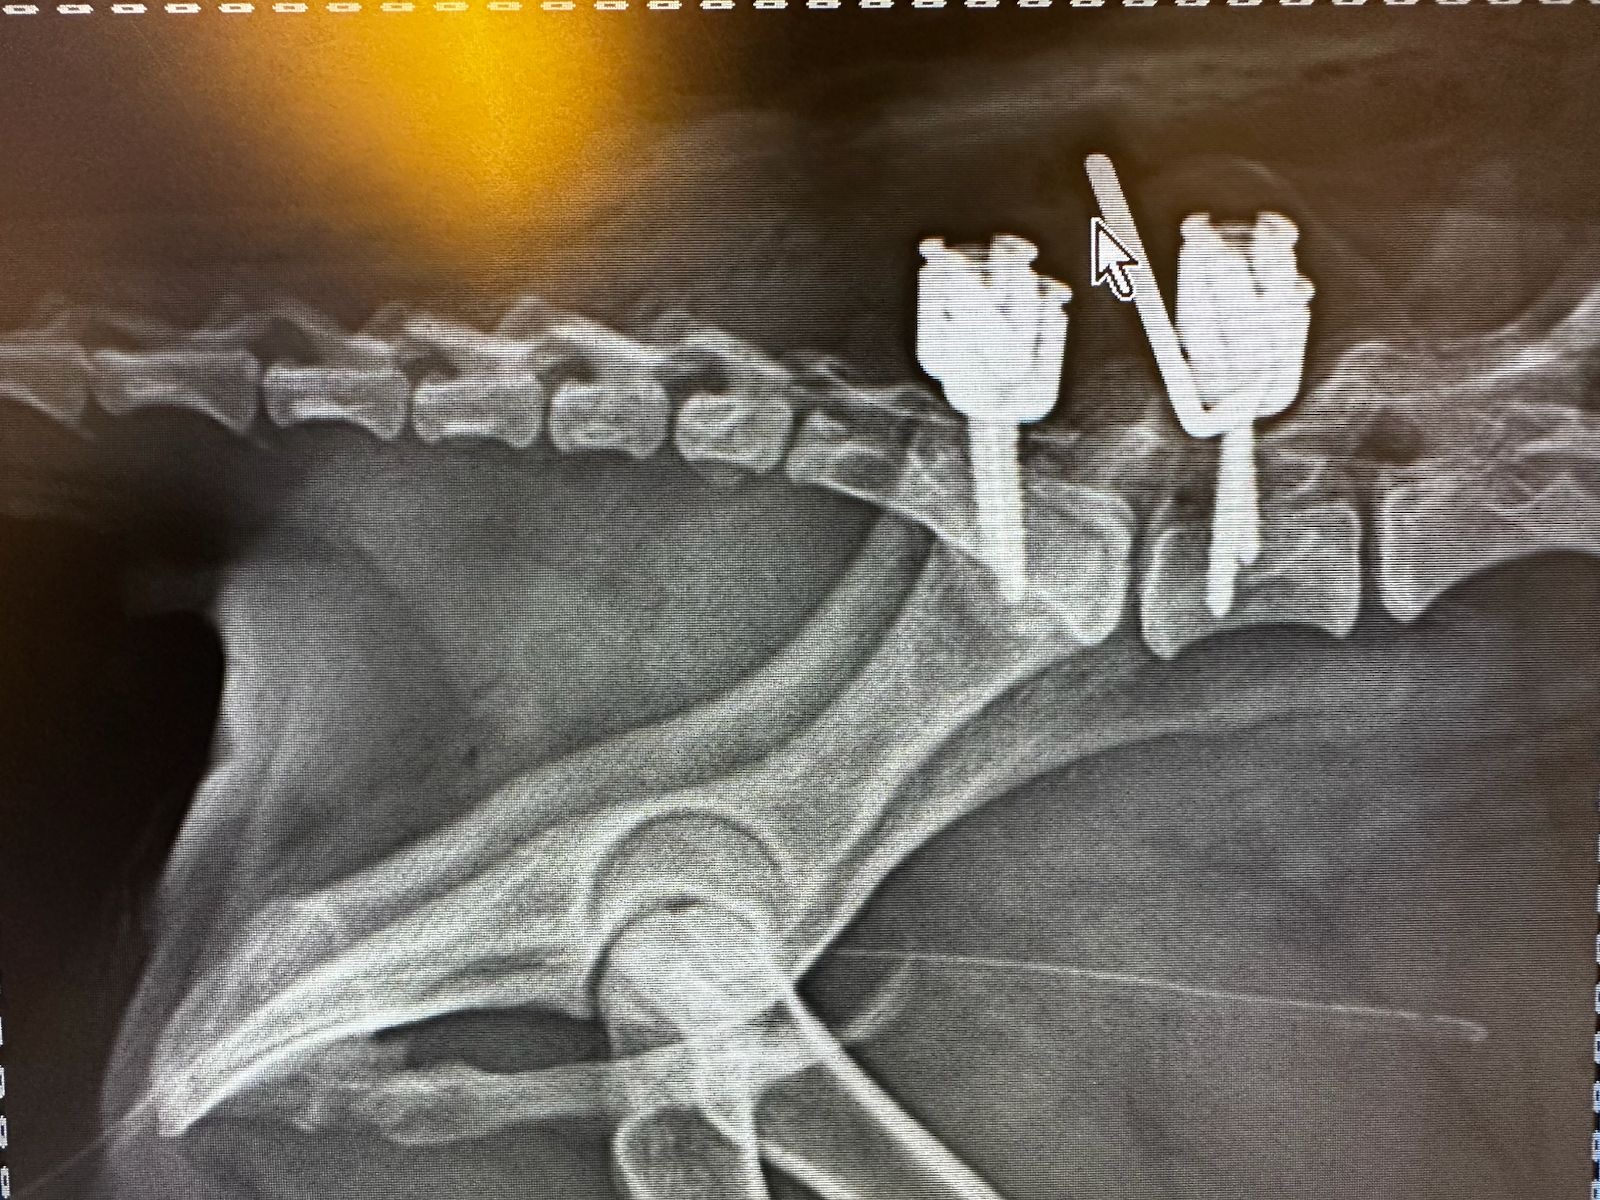

Rayos X y Ultrasonido

Dentro de CENEV contamos con especialistas dedicados al área de imagenología, dedicados al diagnóstico por pruebas como ultrasonido abdominal, radiología de tórax y abdomen, entre otras.

Nuestros equipos y personal especializado permiten estudios rápidos y de alta calidad para apoyar el diagnóstico clínico.